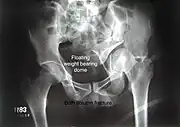

Combined both column fractures | These are the most complex injuries. Here the weight bearing roof or dome of the acetabulum is a floating piece. This adds to complexity of management.

All three x-ray views plus CT scan is a must for diagnosis and management of this complex injury.

Like any other acetabular fracture, if the femoral head is dislocated out of the socket, early reduction into socket is a priority. However, in this injury, non-operative treatment rarely gives satisfactory results. Surgical management is ideal. The choice of approach rests with the surgeon, but going from front, or anterior approach is must. The posterior injury may be tacked with anterior approach by experienced surgeon. If the patient is unfit to undergo major surgery due to any reason, longitudinal traction to achieve secondary congruence of hip may help to restore hip function, though partially. |

Both column fracture showing floating weight bearing dome